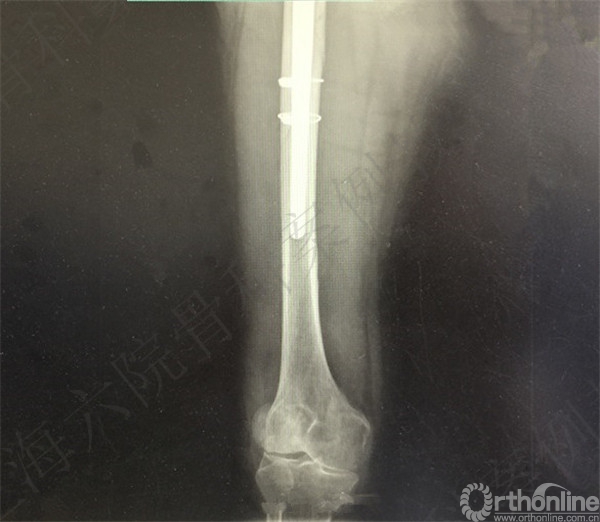

患者2周后自行下地摔倒至右髋假体周围骨折,假体松动,择期行长柄假体置换术+假体周围骨折切开复位内固定术。

术后X线摄片示:假体在位,骨折对位对线可。